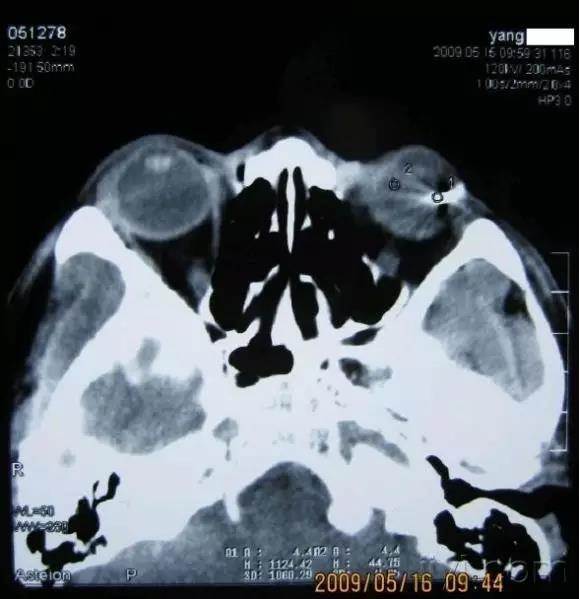

入院后眼球B超未见球内异物回声,拟行异物取出并白内障摘除人工晶体植入术,常规CT检查发现球内异物,体积较大,且与肉眼所见异物的位置大小形状完全不符合,再眼眶摄片发现确实球内存在异物。手术暂停。建议病人到上级医院行玻切。